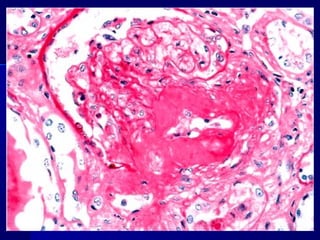

Amiloidosis (hialinización) de un islote del páncreas de un paciente

con diabetes mellitus de tipo 2

Amiloidosis (hialinización) deun islote del páncreas de un paciente con diabetes mellitus de tipo 2